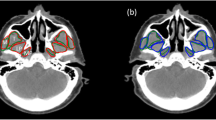

Materials and methods Anatomical information about the muscles of mastication in MR images is used to obtain the spatial relationships relating the muscle region of interest (ROI) and head ROI. A model-based technique that involves the spatial relationships between head and muscle ROIs as well as muscle templates is developed. In the segmentation stage, the muscle ROI is derived from the model. Within the muscle ROI, anisotropic diffusion is applied to smooth the texture, followed by thresholding to exclude bone and fat. The muscle template and morphological operators are employed to obtain an initial estimate of the muscle boundary, which then serves as the input contour to the gradient vector flow snake that iterates to the final segmentation.

Results The method was applied to segmentation of the masseter, lateral pterygoid and medial pterygoid in 75 images. The overlap indices (κ) achieved are 91.4, 92.1 and 91.2%, respectively.